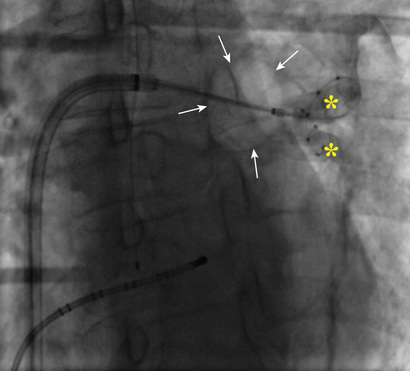

In 2010 a cryoballoon catheter designed to isolate PVs became widely available for use in the United States. In contrast to point-by-point RF ablation around the PVs, the cryoballoon was designed to fit into the antrum of a PV and to create a circumferential ablation lesion using cryoenergy. Cryoenergy is delivered through the entire distal half of the second-generation cryoballoon catheter currently in clinical use. Complete occlusion of the PV by the inflated balloon is necessary for reliable PV isolation (Fig. 38.9). Two 4-minute applications of cryoenergy initially were recommended for each of the PVs. With the second-generation cryoballoon catheter, a single 3- or 4-minute application of cryoenergy often is sufficient to create durable PV isolation in a majority of PVs (Fig. 38.10). Among patients with paroxysmal AF, with a mean of 1.1 to 1.7 applications of cryoenergy per PV, 1-year freedom from recurrent AF was 80% to 82% using a single-freeze protocol.61,62

Avoidance of entry of the cryoballoon into the luminal portion of a PV is important to avoid PV stenosis. The most commonly used cryoballoon catheter has a 28-mm diameter when the balloon is fully inflated. The relatively large size of the balloon typically allows occlusion of a PV from the antrum. With use of the 28-mm balloon, up to 40% of the posterior wall between the left and right PVs is rendered electrically silent.63